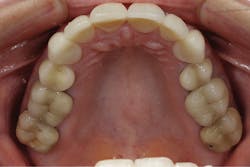

A 52-year-old female patient presented to my office with recent porcelain restorations that had been placed on her upper six anterior teeth. Besides her complaint of the bite feeling different, her main concern was that her speech was off, especially her s sounds. She stated these problems occurred after the final crowns were placed. Further questioning also revealed that she was unhappy with color and shape (figures 1–3). A full examination was completed, including x-rays and photographs, and periodontal, TMJ, occlusion, and dentition evaluations. She had excellent oral health and her dental issues were all related to her occlusal and esthetic complaints.

Figure 3: Maxillary occlusal view of the patient’s original restoration